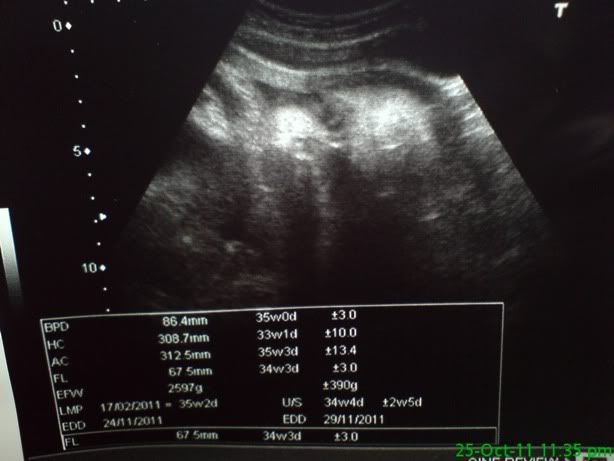

我的宝宝2.7kg,突然慢下来了。。。